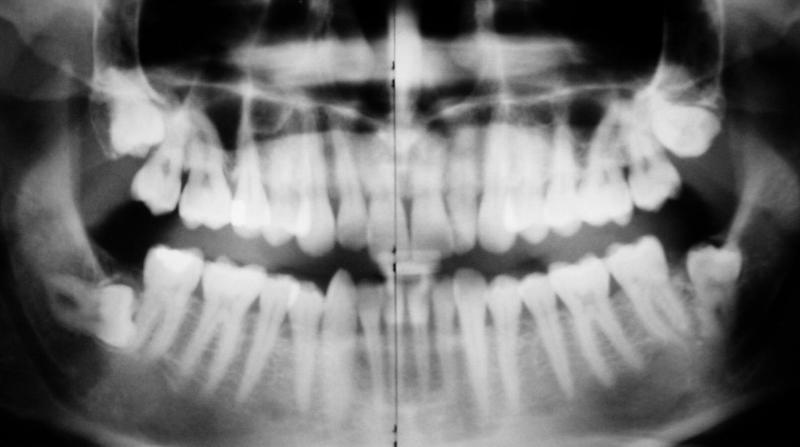

Bernd-Kiefer-totale